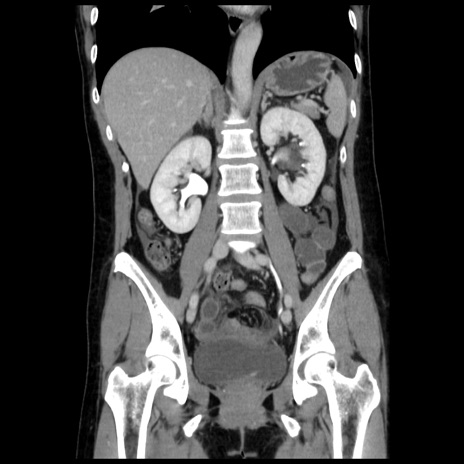

症例10(冠状断像)

【症例】 50歳代女性

【主訴】 腹痛

【現病歴】前日生レバーを食べた。今朝に排便あり。 昼前に突然発症の腹痛を生じ、当院救急外来を受診した。

【既往歴】 子宮筋腫にてで子宮全摘後

【身体所見】 意識清明、腹部:平坦、軟、下腹部やや左を中心に圧痛・反跳痛あり、筋性防御あり

【データ】WBC 7800、CRP 0.07